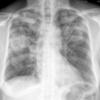

Abscess CT